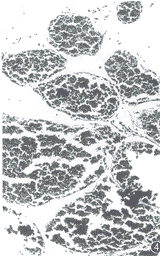

例1 男,65岁。下胸部束带感伴双下肢无力、行走不稳 4个月余。体检:T6以下浅感觉明显减退,双腹壁反射、提睾反射消失,双侧巴彬斯基征(+),双下肢肌力 IV级。脑脊液压力和常规检查正常。胸椎 X线片正常。 MRI扫描:T5~6水平椎管内脊髓后方硬膜外见一4.4 cm×1.5 cm大小的梭形病灶,基底靠后,最大处向两侧椎间孔方向生长。脊髓明显受压变细、前移。T1WI病灶与脊髓呈等信号(图1),T2WI上与脑脊液信号相似(图2)。注射钆喷替酸葡甲胺(Gd-DTPA)后,病灶呈明显均匀强化(图3)。MRI诊断:神经根瘤。手术所见:T5~6椎管内硬膜外见一肉红色梭形肿瘤,边界清楚,呈分叶状, 与硬脊膜有轻度粘连。未见明显增粗的供血动脉和引流静脉。邻近椎板和棘突骨质疏松,但无破坏。病理检查:肿瘤组织由大片壁薄、管腔扩大互相吻合、大小不一、外形不规则的血管间隙构成,壁为单层内皮细胞。血管间见散在的淋巴细胞和脂肪细胞(图4)。病理诊断:海绵状血管瘤。

图1~4 例1。 T1WI(图1)示 T5~6椎管内脊髓后方硬膜外梭形肿块与脊髓信号相等, 脊髓明显受压前移、变细,基底靠后。T2WI(图2)示病灶呈均匀高信号与脑脊液信号相似。注射钆喷替酸葡甲胺(Gd-DAPA)后(图3)病灶显著均匀强化。镜检(图4):肿瘤主要由扩张而大小不等的血管间隙构成,壁薄,由单层内皮细胞构成(HE 20×10)